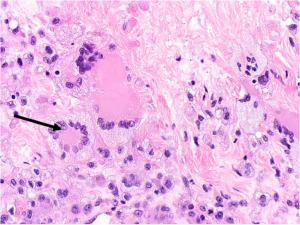

Histopathologically, non-ulcerated NXG lesions are characterized by normal epidermis and superficial dermis. Palisading xanthogranulomas with lymphoplasmacytic infiltrate and zones of necrobiotic collagen are seen in the mid-dermis and subcutaneous tissue (Figure 1A). Cholesterol clefts and both Touton giant cells and large, bizarre foreign body giant cells are other classic features (Figure 1B).[3]